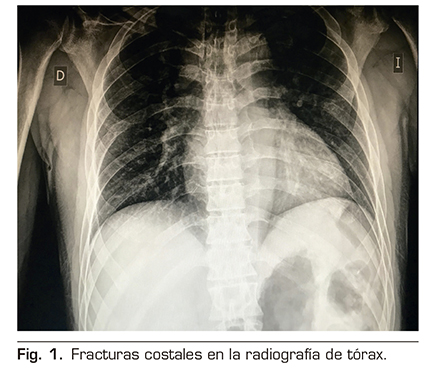

A la exploración física presentaba unas cifras de tensión arterial 150/90 mmHg, saturación arterial de O2 de 96 % al aire ambiente, murmullo vesicular conservado, no focalidad neurológica y dolor importante a la palpación de la pared costal izquierda. En los estudios de imagen realizados se evidenciaron múltiples fracturas costales en el hemitórax izquierdo, desde la 6.ª a la 9.ª costillas, sin evidencia de afectación pleuropulmonar aguda (Figura 1).